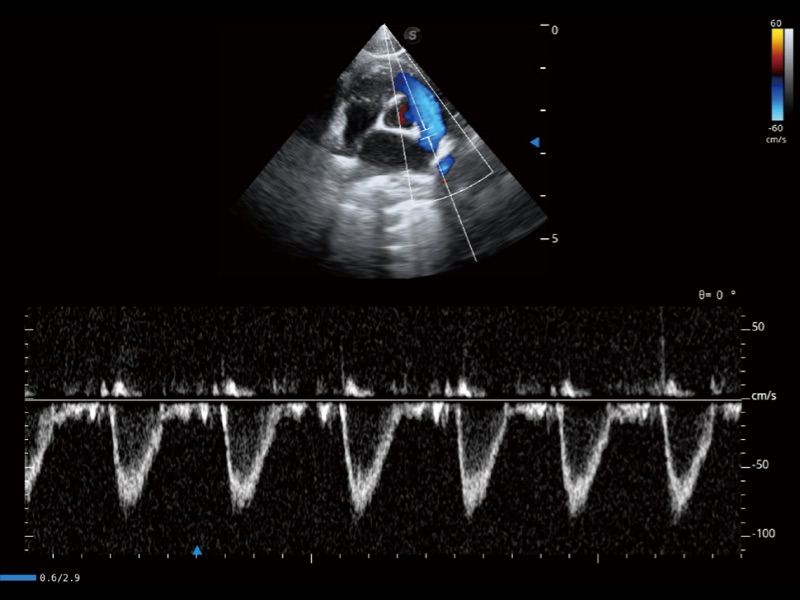

通過創(chuàng)新的 Matrix E自適應(yīng)濾波器和超長(zhǎng)時(shí)間域算法,極大提升超低速微細(xì)血流的檢出能力,同時(shí)更精準(zhǔn)地濾除軟組織和噪聲信號(hào),為獸用醫(yī)生提供以往無法通過常規(guī)血流獲得的疾病診斷信息。

通過色彩血流和實(shí)時(shí)寬景相結(jié)合,可觀察到完整的靜脈或動(dòng)脈的血流,方便醫(yī)生檢查。實(shí)時(shí)掃查過程中,如有任何操作失誤也可以很容易地進(jìn)行回掃擦除,而不會(huì)中斷掃查。